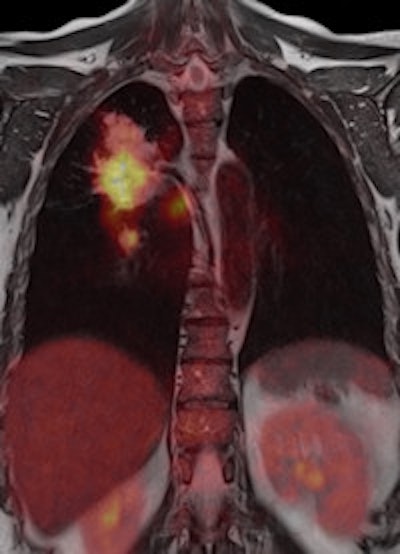

Left: To improve the precision of spatial registration, the Biograph mMR system collects MR and PET data simultaneously from a single frame of reference. The result is a combined MR and PET scan acquired at the same point in time and reflecting the same point in the physiologic processes such as respiration. Right: The benefits of MRI in the study of neurological diseases are well-known and established, and it can lead to a better understanding of neurological pathologies. Images courtesy of Siemens.Philips has been working on its latest MR technology for almost as long as the search for a practical PET/MR hybrid. After an eight-year development project, the company is promoting its Ingenia 1.5- and 3-tesla systems, which it describes as the world's first digital broadband MR unit. This incorporates dStream architecture, which digitizes the signal directly in the coil. Vendors have been looking for ways to shorten the analogue part of the signal processing pathway because this offers the potential for reducing signal loss and noise. The Philips approach goes further by digitizing the signal within the coil itself and transporting it via a fiber-optic cable to the acquisition electronics contained in the scanner cabinet, explained Maurits Wolleswinkel, global lead for MR marketing.